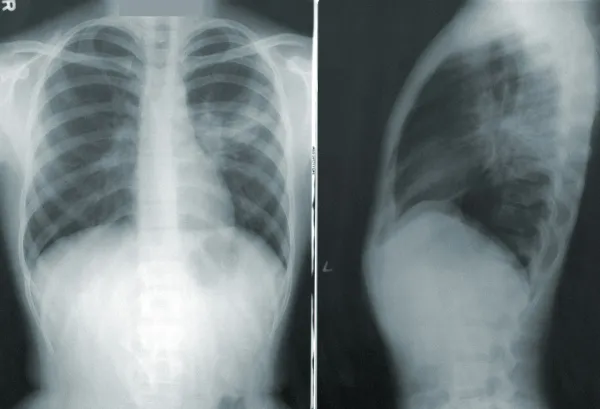

Выявить патологические изменения можно после проведения компьютерной томографии.